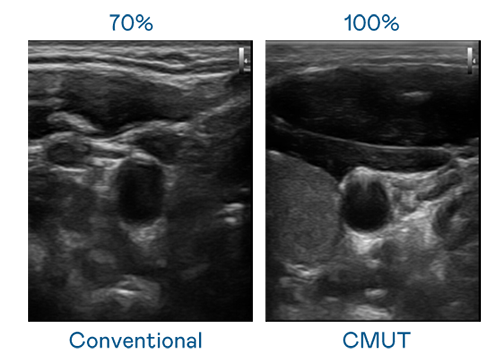

CMUT 技術是一種用電容式微機電元件來產生超音波訊號的技術。與傳統 PZT 壓電式技術相比,CMUT 頻寬增加 30%,更寬頻的超音波訊號讓影像解析度大幅提升,是實現高影像品質醫療超音波掃描、促進精準醫療發展的關鍵技術。

超音波影像的解析度高低,首先取決於探頭能發出的訊號頻寬。英国正版365 CMUT 可提供高清晰的超音波訊號,提供高頻寬、高靈敏度、影像紋理細節更高的超音波影像,協助醫護人員縮短影像判讀時間及利用精準的醫療影像進行診斷。